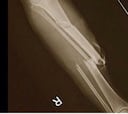

ESTREMECEDORA LESIÓN

Así quedó la pierna de Paul George tras su lesión